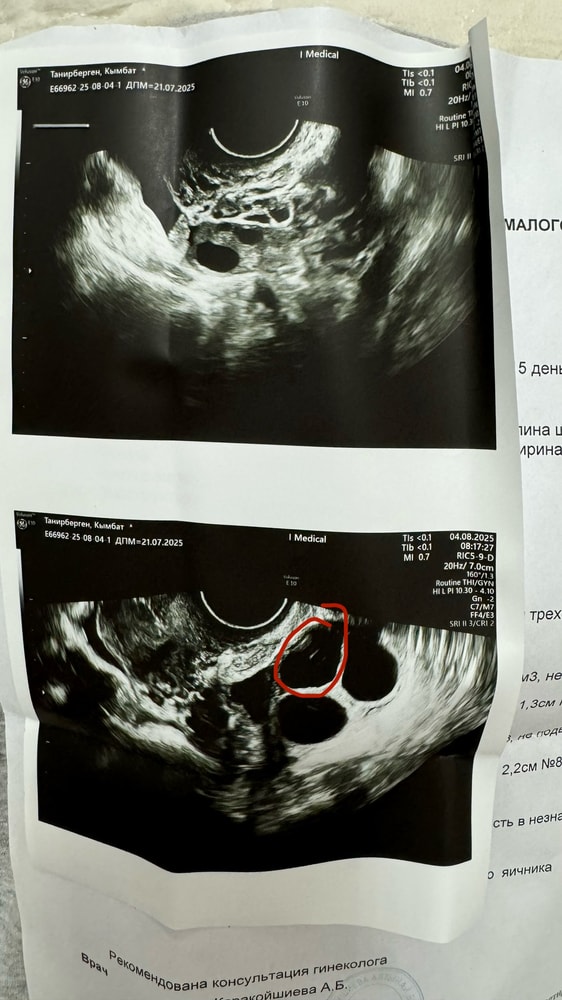

У вас стимуляция была? Как будто 2 дф и ЖТ рядом

Аня, ну конечно это ЖТ, оно такое кудрявое, а фолликулы более округлые. Только после появления ЖТ уже навряд ли те два дф лопнут, т.к там уже прогестерон возымел силу. Удачи вам в этом цикле 🫶🏻

Аня, да, оно кудрявое и в нем часто какие-то включения бывают внутри, как взвеси. А фолликул четко овальный либо круглый полностью черный.